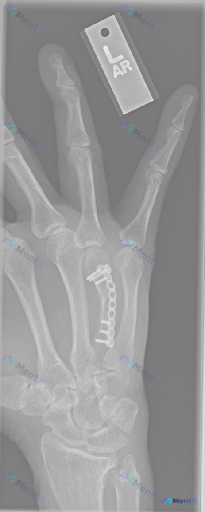

整理到一张左手正位X光片的术后复查资料,标注“L”,覆盖掌骨、近端指骨及部分腕关节。

- 第3掌骨有钢板+多枚螺钉固定,形态和骨干弧度基本匹配

- 第3掌骨干能看到透亮线

- 透亮线附近有模糊的骨痂影

- 周围软组织没看到明显肿胀,也没肿块或钙化

- 掌指、指间关节间隙清晰,没有脱位